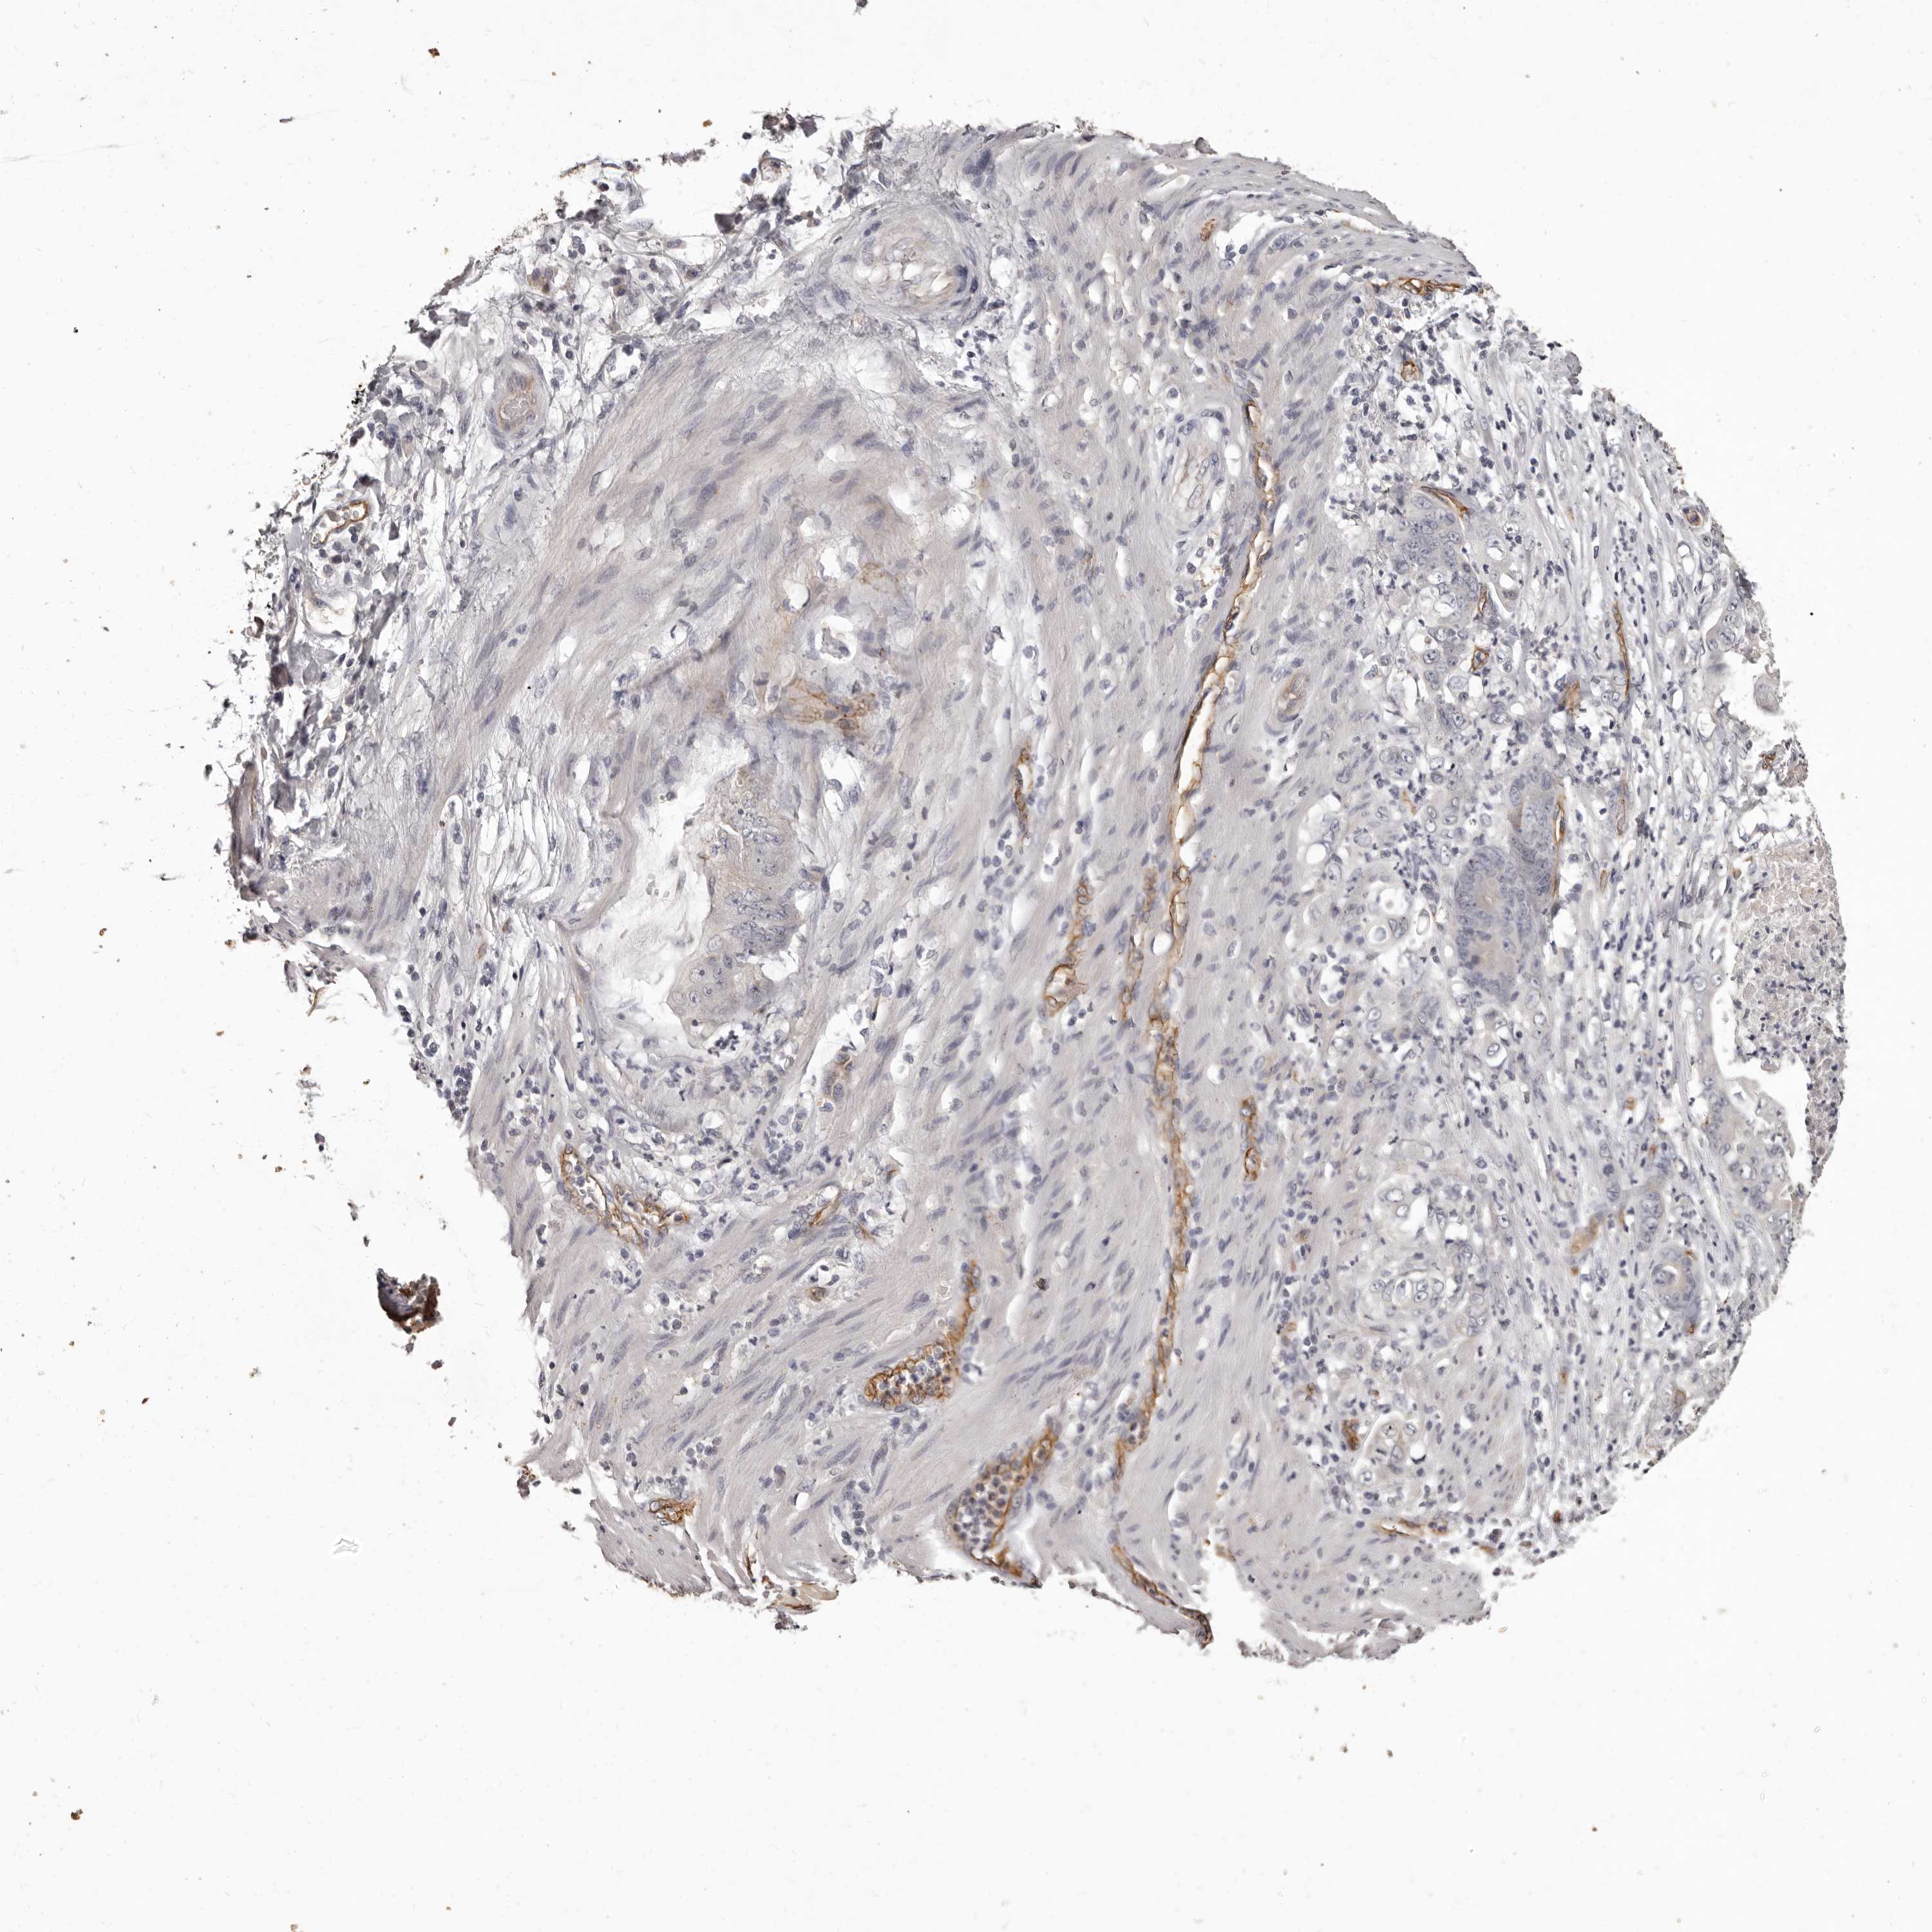

STOMACH CANCER - Protein expressioni

A mouse-over function shows sample information and annotation data. Click on an image to view it in a full screen mode. Samples can be filtered based on level of antibody staining by selecting one or several of the following categories: high, medium, low and not detected. The assay and annotation is described here.

Note that samples used for immunohistochemistry by the Human Protein Atlas do not correspond to samples in the TCGA dataset.

Antibody stainingi

Antibody staining in the annotated cell types in the current human tissue is reported as not detected, low, medium, or high, based on conventional immunohistochemistry profiling in selected tissues. This score is based on the combination of the staining intensity and fraction of stained cells.

Each image is clickable and will lead to virtual microscopy that enables deeper exploration of all samples and also displays staining intensity scores, fraction scores and subcellular localization as well as patient and tissue information for each sample.

Antibody HPA013209

Staining

High

Medium

Low

Not detected

Intensity

Strong

Moderate

Weak

Negative

Quantity

>75%

75%-25%

<25%

None

Location

Nuclear

Cytoplasmic/membranous

Cytoplasmic/membranous,nuclear

Adenocarcinoma, NOS